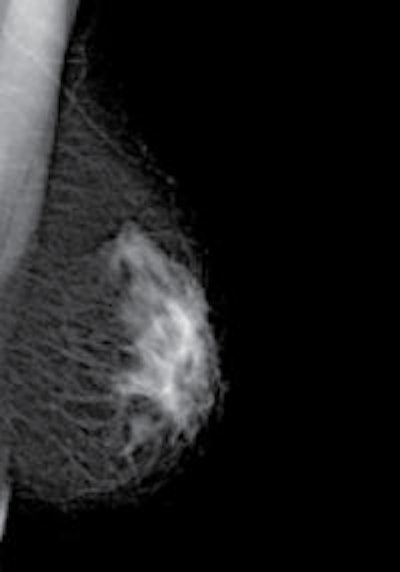

The photon-counting technology used by MicroDose allows for single-shot spectral image acquisition, which is currently under development. (Provided by Philips)

"The photon-counting technology used by MicroDose allows for single-shot spectral image acquisition, which is currently under development. The spectral information would come as a bonus to the normal mammogram since it is acquired in the same exposure, without compromising image quality or increasing dose. The radiologist will thus be able to obtain additional information from the mammogram without additional radiation dose and additional exposure time," she explained.